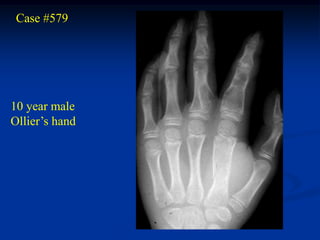

Case #579

10 year male

Ollier’s hand